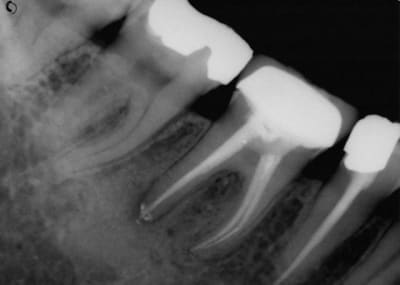

J'avais couronné... mais démontable, pas d'IC...

3 ans après (oui, on devait surveiller tous les 3 mois ;-)

(radio 3 mois après)

Voilà la fin.

Les deux dernières sont de 2011 et 2015.

Tout ça pour dire que les voies de l'endo sont parfois impénétrables...